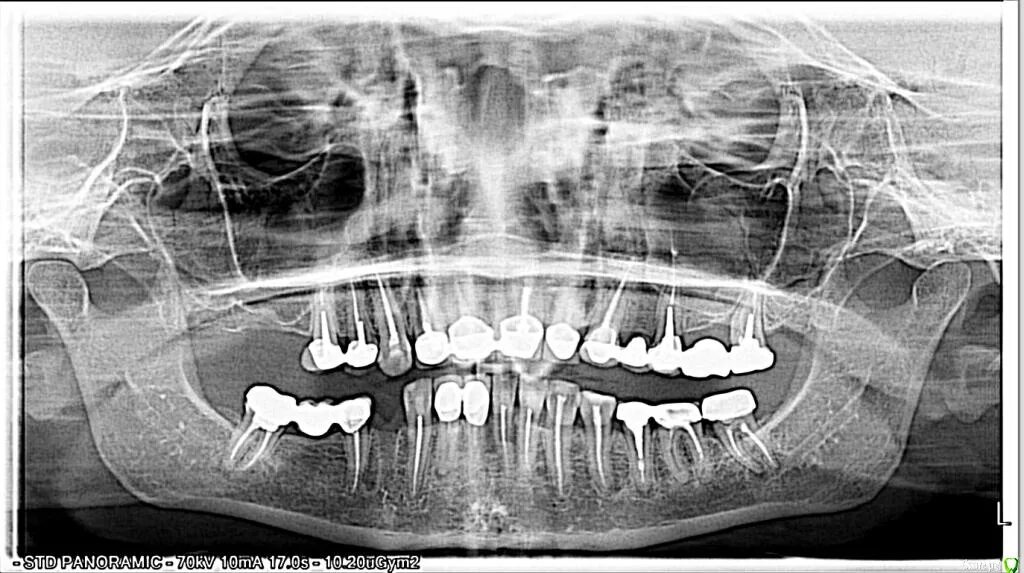

Онемение губы и подбородка